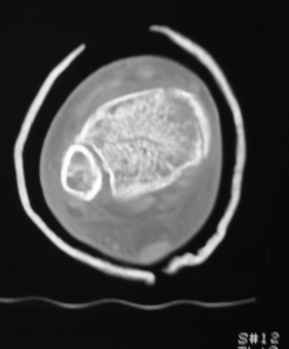

Остеопороз (продолжение 3) - данные КТ

Юрий Алексеевич Булахтин 07 Ноябрь 2009, 16:27

|

Уважаемые коллеги!

Продолжая тему представляю данные КТ нашей пациентки.

Вопросы к сообществу - в сообщении №2.

Юрий Алексеевич Булахтин